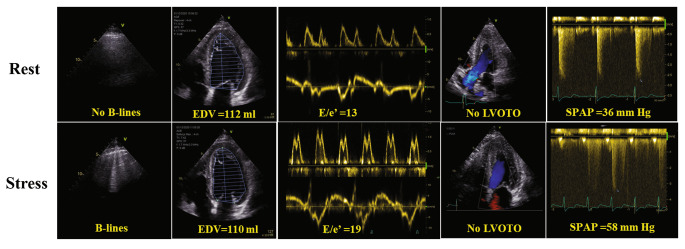

• RFR: dyspnea

• 58-year-old female

• PHT 141 ms, MVA 1.6 cm2

• Mild to moderate regurgitation

Case

Wiley BM, et al. (2020) Lung Ultrasound During Stress Echocardiography Aids the Evaluation of Valvular Heart Disease Severity. JACC Cardiovasc Imaging 13:866-72.

• B-lines are a result of dynamic elevation in LA pressure due to mixed MR/MS

• MV disease causing exercise induced pulmonary edema, in combination with increase in MG and RVSP, helps classify valve as hemodynamically severe

• Patient underwent MVR post stress test